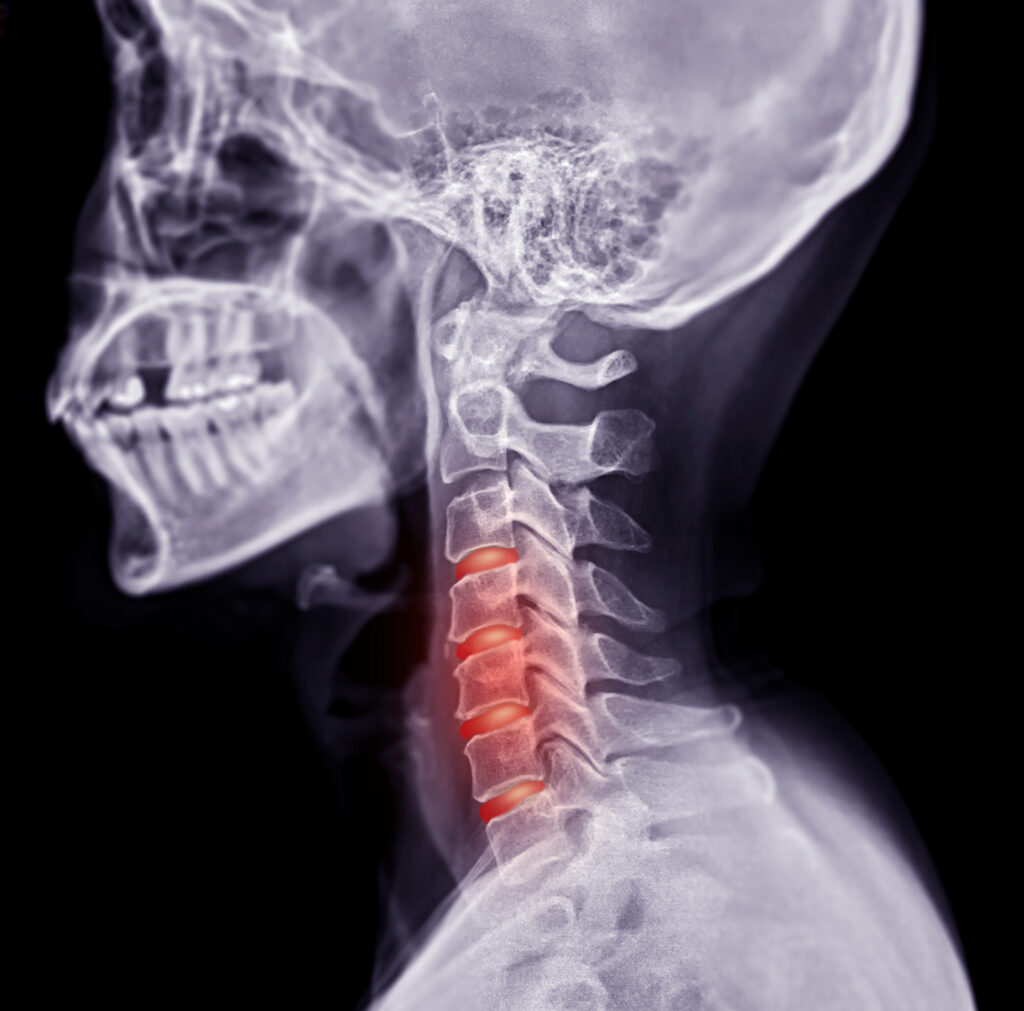

Neck pain can result from many causes, including degenerative disc disease, arthritis, herniated discs, poor posture, or past injuries. When it becomes chronic, pain may radiate to the shoulders, arms, or head, sometimes leading to headaches or nerve-related symptoms.

• Imaging studies (X-ray, MRI, or CT) if needed